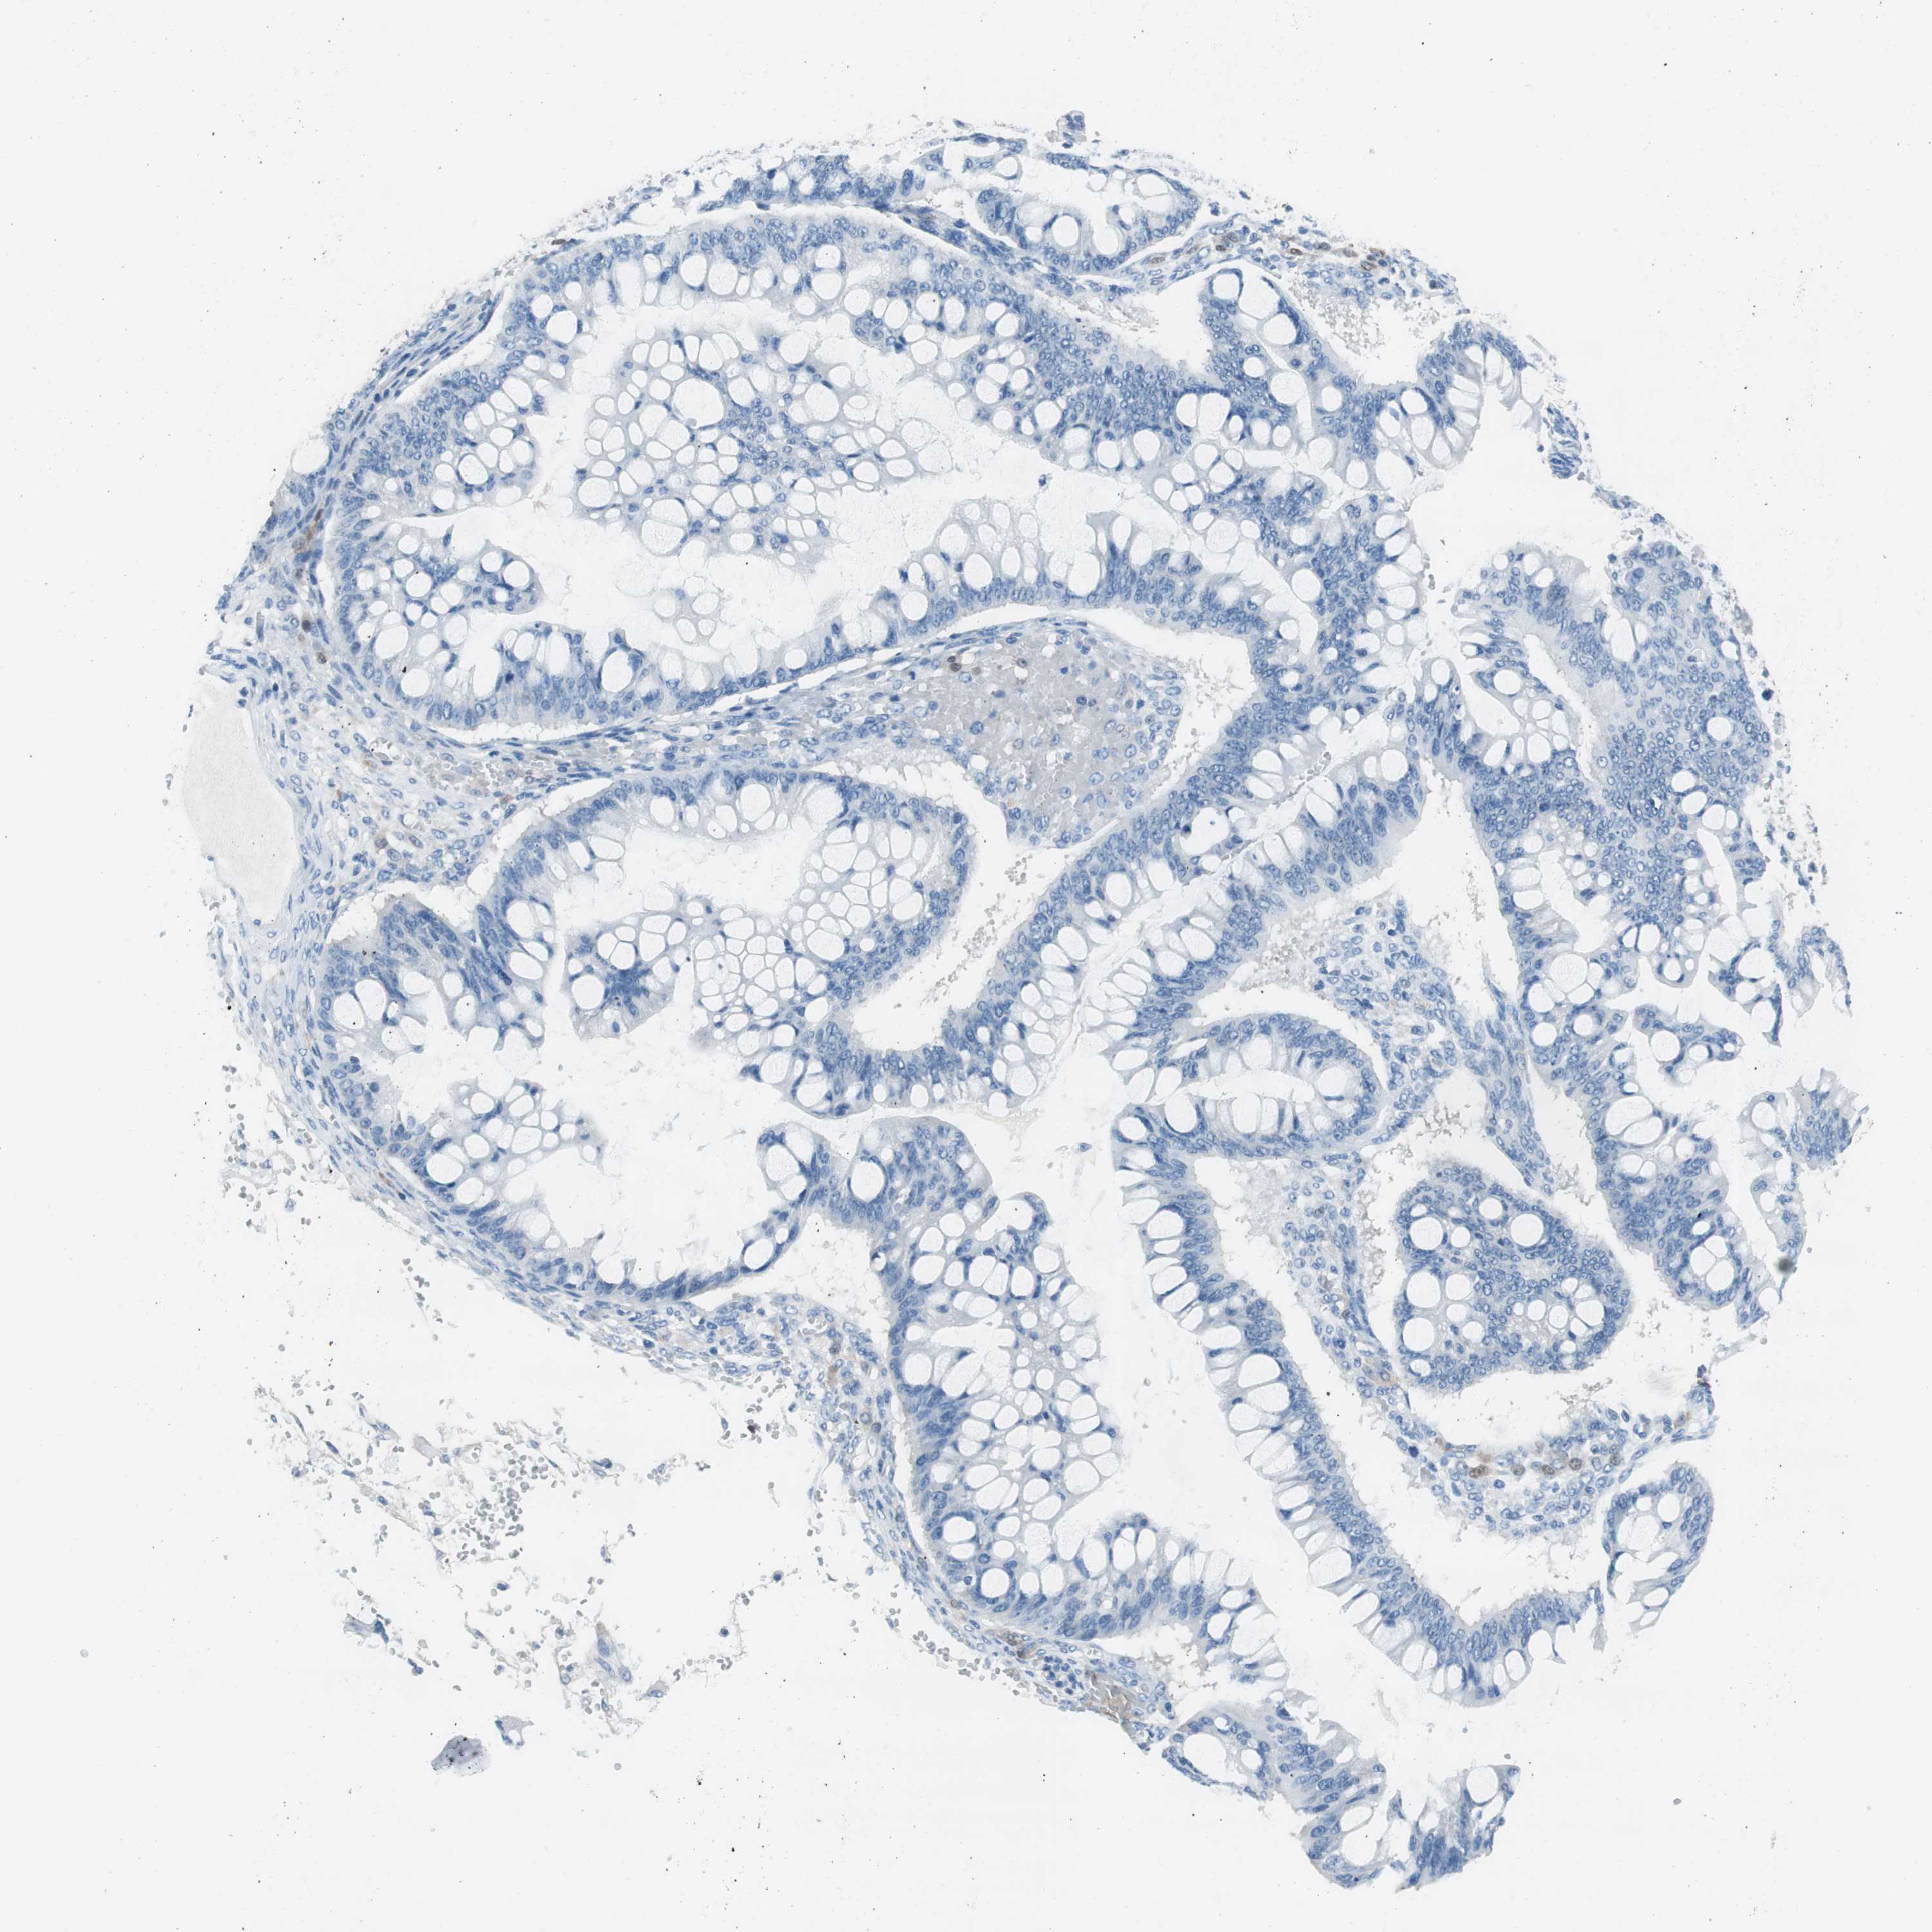

OVARIAN CANCER - Protein expressioni

A mouse-over function shows sample information and annotation data. Click on an image to view it in a full screen mode. Samples can be filtered based on level of antibody staining by selecting one or several of the following categories: high, medium, low and not detected. The assay and annotation is described here.

Note that samples used for immunohistochemistry by the Human Protein Atlas do not correspond to samples in the TCGA dataset.

Antibody stainingi

Antibody staining in the annotated cell types in the current human tissue is reported as not detected, low, medium, or high, based on conventional immunohistochemistry profiling in selected tissues. This score is based on the combination of the staining intensity and fraction of stained cells.

Each image is clickable and will lead to virtual microscopy that enables deeper exploration of all samples and also displays staining intensity scores, fraction scores and subcellular localization as well as patient and tissue information for each sample.

Antibody HPA008055

Staining

High

Medium

Low

Not detected

Intensity

Strong

Moderate

Weak

Negative

Quantity

>75%

75%-25%

<25%

None

Location

Nuclear

Cytoplasmic/membranous

Cytoplasmic/membranous,nuclear

Cystadenocarcinoma, serous, NOS

Carcinoma, endometroid

Carcinoma, NOS

Cystadenocarcinoma, mucinous, NOS